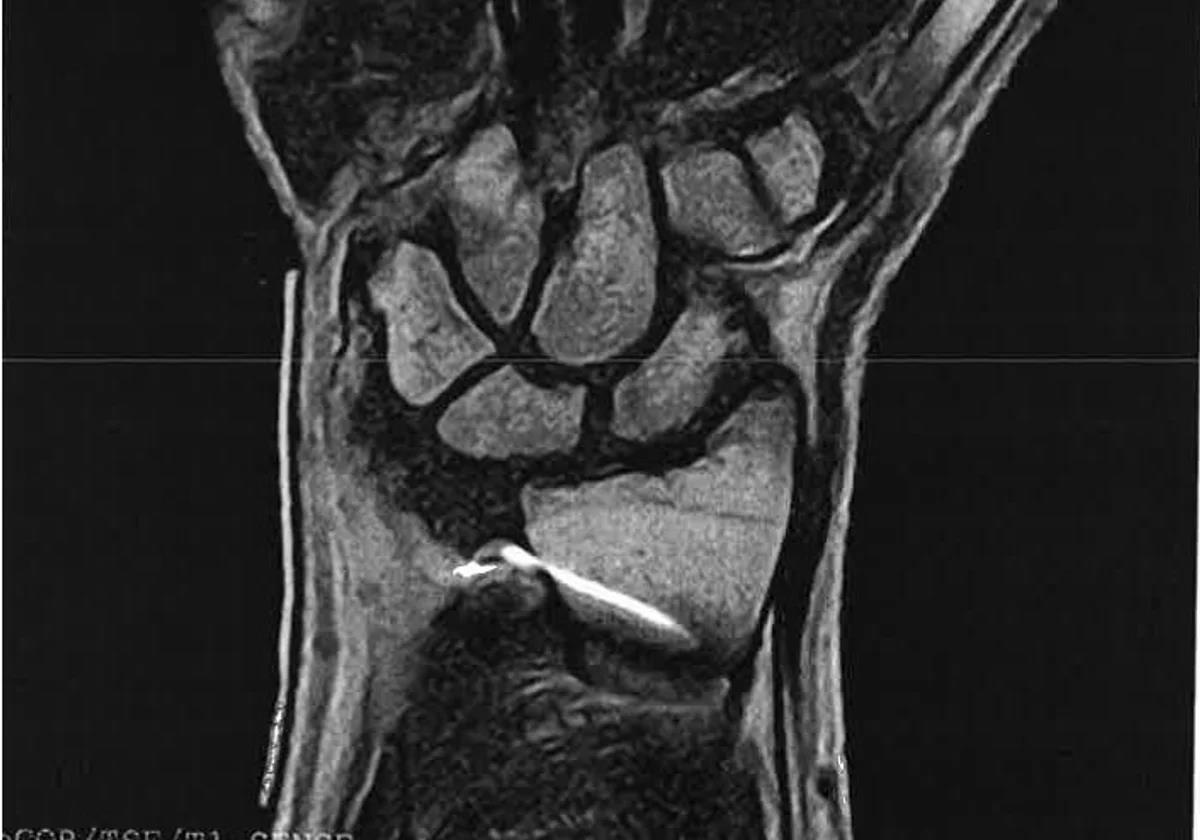

Image of the needle located in the woman's left wrist. SUR

It was not until October of that year - some seven months later - when an MRI, prompted by the discomfort, revealed that the patient had “a metallic object, likely from a previous surgical procedure,” inside her wrist.